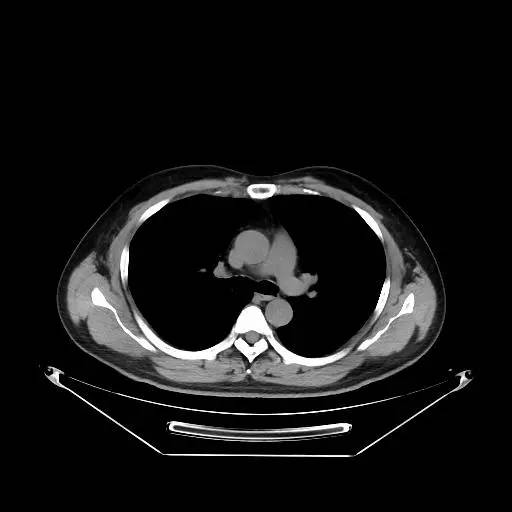

男,47岁,查体发现右肺小结节8月余。

[影像描述]

右肺上叶可见直径约7mm磨玻璃样结节,其内见空泡影,有浅分叶及血管集束征象,增强扫描无强化,余肺、纵隔未见明显异常。

右肺上叶不典型腺瘤样增生(AAH)

AAH的影像学特点为呈类圆形小病灶,边界清楚,淡至中等密度均匀的毛玻璃或磨砂玻璃阴影,不遮蔽其下的肺实质,多数在5 mm以下。